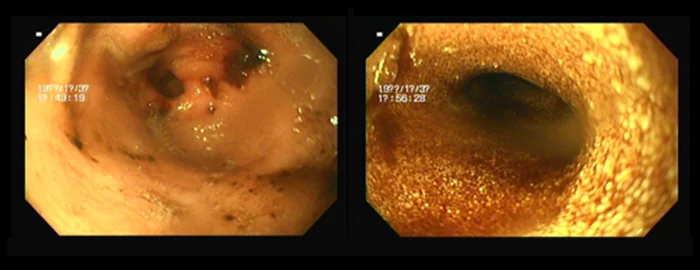

2. 내시경 검사 (Endoscopy)

위장관 내부를 직접 관찰하여 염증, 궤양, 종양 등의 병변을 진단합니다. 필요시 조직 생검을 통해 정확한 병리학적 평가가 가능합니다.

(예: 간염 환자의 경우, 협진을 통해 복강경 생검 고려) 이물 제거 등 치료적 시술도 일부 가능합니다.